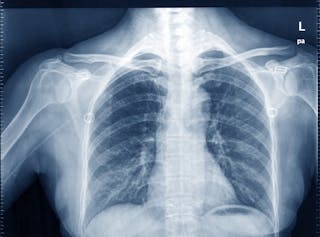

‘raios X’ ou radiografia planar

esta é ainda a forma mais comum, amplamente disponível e mais simples de imagem médica, muitas vezes usada para ver um osso partido. Raios-X são na verdade fótons, ou pequenos pacotes de energia (referidos como radiação ionizante) e formam parte do espectro eletromagnético (assim como a luz visível, microondas e ondas de rádio).

como um feixe de raios x passa através do tecido humano, estes fótons de raios x podem ser absorvidos e desviados por estruturas de tecidos densos, como o osso, e não podem sair do corpo. Outros fótons de raios-x podem encontrar tecido que é menos denso (como músculo) e são capazes de passar por isso facilmente e sair do corpo.

a saída de fótons de raios-x, em seguida, chegar a um receptor de imagem digital ou detector onde eles fornecem um padrão de densidade de tecidos para o receptor digital para converter na imagem de raios-x (ou radiografia) que estamos familiarizados com.

tecido denso, tal como o osso que atenuou o raio-x, parece denso ou branco; Tecido menos denso, tais como os pulmões que estão cheios de ar, parecem menos densos ou escuros, que observamos com um “raio-X torácico”. Outros tecidos do corpo humano têm densidades entre estes dois extremos e aparecem em uma imagem de raio-x como diferentes tons de cinza.